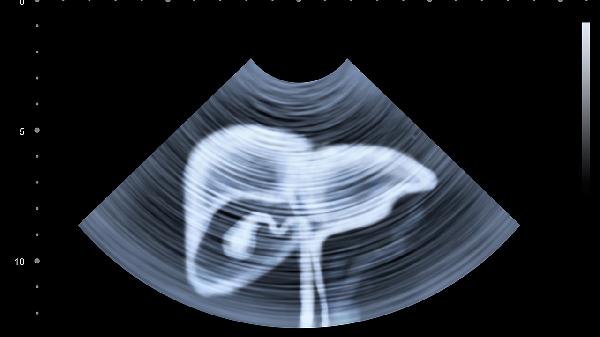

除丙肝外,非酒精性脂肪性肝病也可能引起转氨酶波动性升高。这类患者通常伴有肥胖、胰岛素抵抗等代谢异常,超声检查可见肝脏脂肪浸润。治疗需通过饮食控制、减重和运动改善代谢状态。药物性肝损伤常见于长期服用对乙酰氨基酚片、抗结核药物等肝毒性药物的人群,停药后转氨酶多可逐渐恢复。